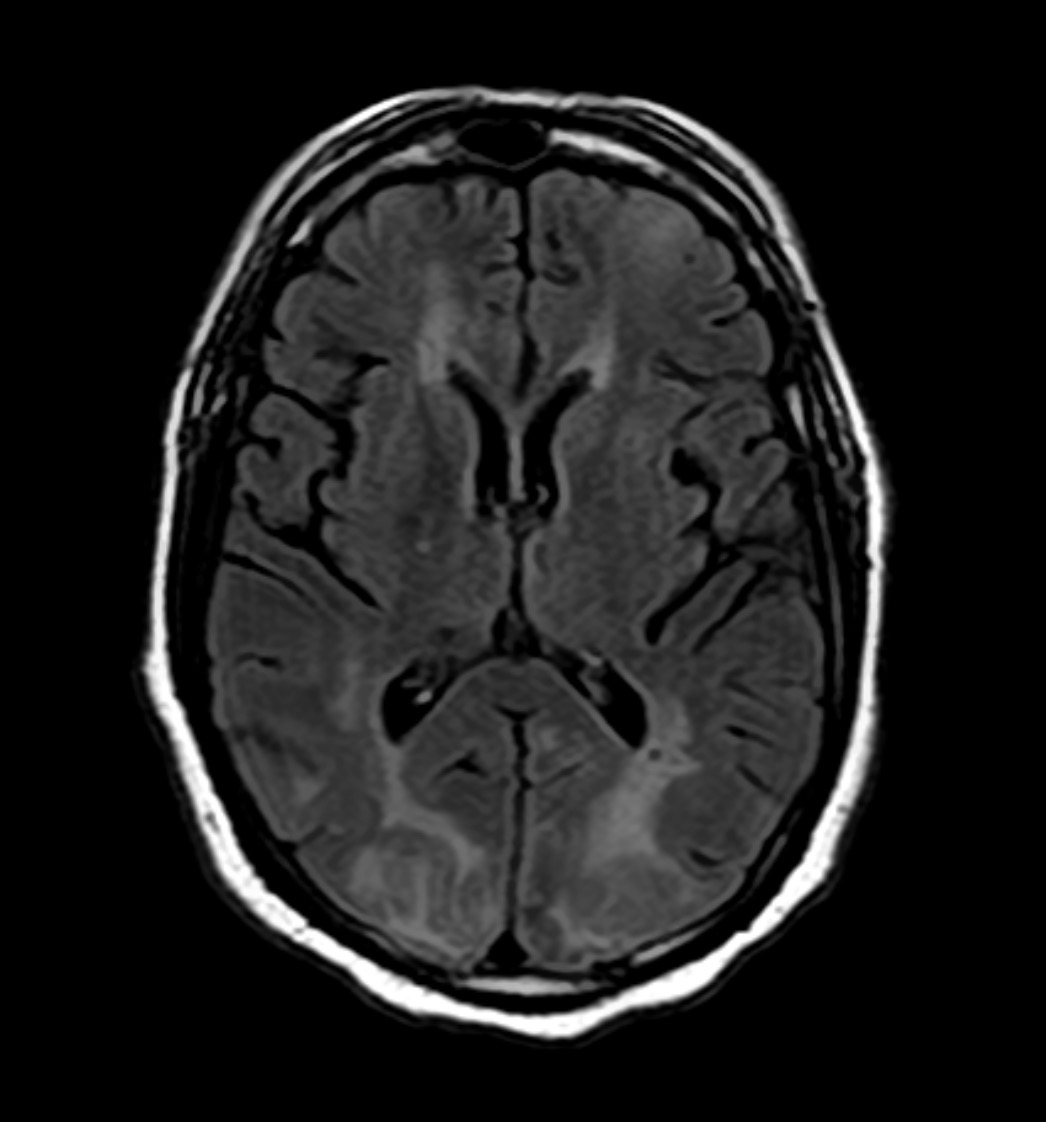

• Diagnosis is clinical, supported by characteristic MRI findings of large, bilateral, asymmetric T2/FLAIR hyperintense lesions without mass effect.

• Lesions are poorly demarcated, often involve both gray and white matter, and rarely show gadolinium enhancement.